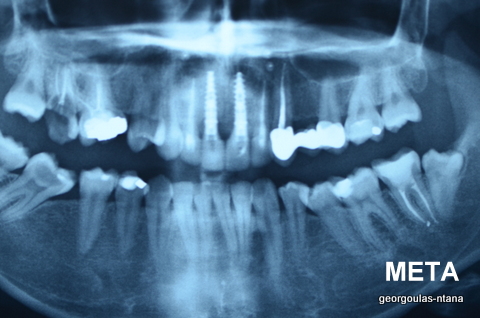

ΟΛΙΚΗ ΑΠΟΚΑΤΑΣΤΑΣΗ ΑΝΩ Κ ΚΑΤΩ ΓΝΑΘΟΥ ΜΕ ΕΜΦΥΤΕΥΜΑΤΑ, ΑΜΕΣΗ ΦΟΡΤΙΣΗ Κ ΑΝΟΙΚΤΗ ΑΝΥΨΩΣΗ ΙΓΜΟΡΕΙΟΥ